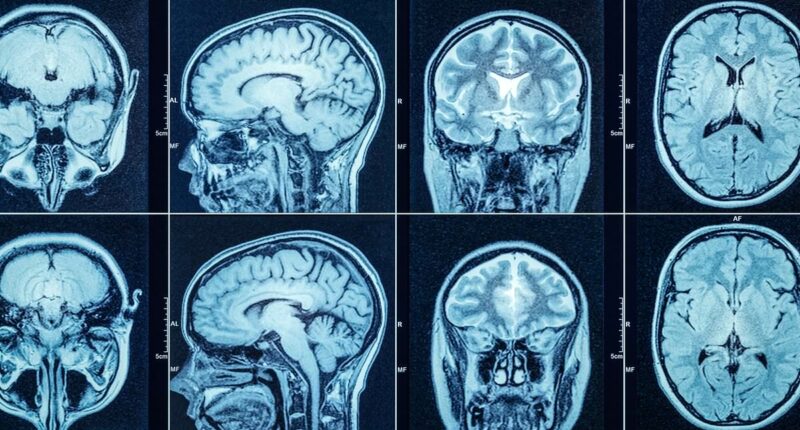

It is infused into the brain using MRI scanning and takes roughly 12 to 18 hours of neurosurgery.